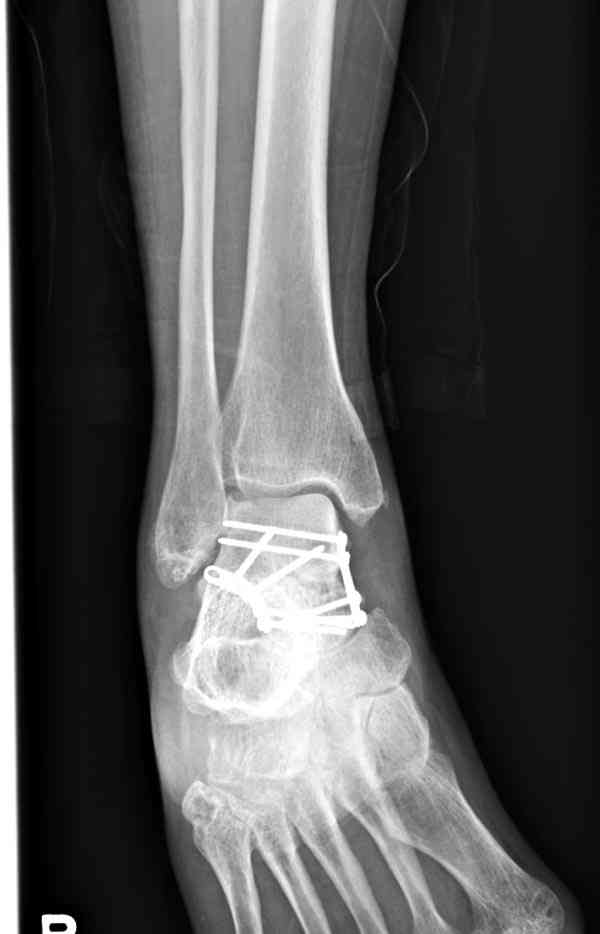

Случай с множественным оскольчатым переломом тарана оперированный из двойного доступа.

Через 14 мес.: